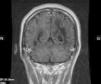

Se efectuó resonancia magnética por imágenes (RMI) con contraste en la que se observó extensa lesión subcortical en lóbulo frontal, parietal y occipital izquierdos, con extensión al esplenio del cuerpo calloso y mesencéfalo superior del lado izquierdo, y compromiso de los lóbulos parietal y occipital derechos. Las imágenes predominaban en lóbulos posteriores y dibujaban las fibras subcorticales en «U». No hubo realce con el contraste IV, ni efecto de masa sobre estructuras adyacentes de la línea media (figs. 1-5).

El VJC se reactiva ante cuadros de inmunosupresión grave, e induce la infección lítica de los oligodendrocitos con lesiones multifocales de desmielinización. La enfermedad tiene una prevalencia del 1 al 4% entre los pacientes con sida. El curso clínico es progresivo y con déficit neurológico focal en el 80% de los pacientes afectados. El examen del LCR es normal o con alteraciones inespecíficas, (hiperproteinorraquia moderada y pleocitorraquia mononuclear)4. La RM muestra la presencia de lesiones, por lo general bilaterales, simétricas o asimétricas, con predominio en lóbulos parieto-occipitales, bien delimitadas y localizadas en áreas periventriculares y en la sustancia blanca subcortical. Pueden ser únicas o múltiples, no refuerzan con el contraste, no están rodeadas de edema, ni producen efecto de masa, y dibujan las fibras subcorticales en «U» o fibras arcuatas; un tercio de los pacientes tienen compromiso de la fosa posterior. Entre un 5-10% de los casos, esta última localización se revela como la única manifestación de la enfermedad4. El diagnóstico se confirma por la PCR en el LCR. La sensibilidad de la prueba es variable (40-80%), posee una alta especificidad (mayor del 90%) y un valor predictivo positivo del 100%5.